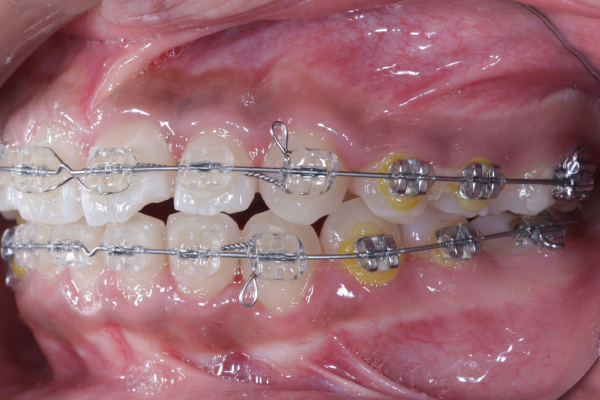

AFTER

【矯正治療開始11ヶ月】

11ヶ月経ち歯のガタガタが改善し、歯並びが綺麗になってきています。